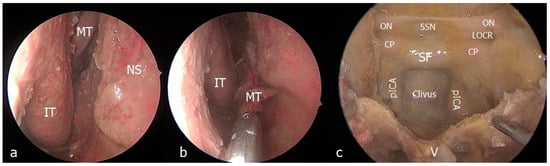

- The nasal step

- The maxillary step

- The petrosal step